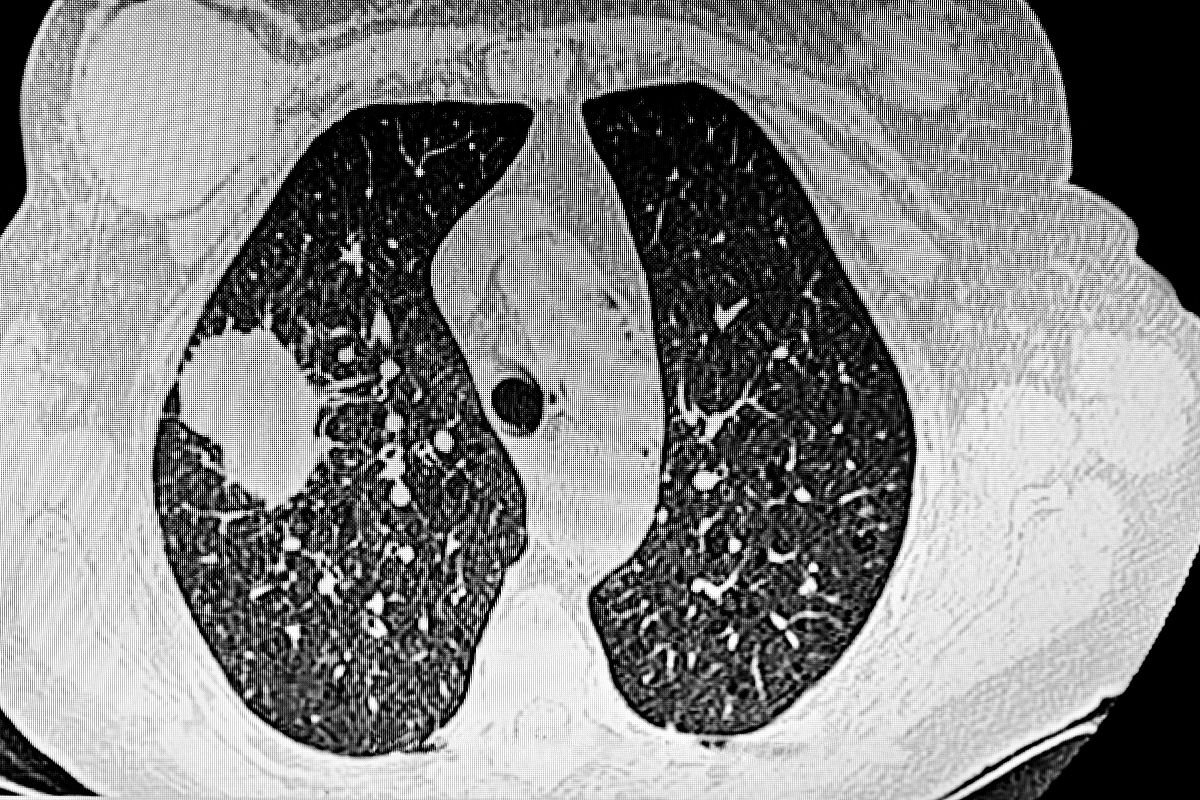

肺上有结节且喘不上气,多因结节影响肺部功能或合并其他肺部问题。若结节体积较大(直径超过3厘米),或位于支气管、肺门等关键位置,会压迫气道或阻碍肺部通气,导致气流不畅,出现呼吸困难、喘憋症状。

也可能是结节合并肺部炎症、肺气肿等疾病,炎症会导致肺组织充血水肿,肺气肿会使肺功能下降,两者叠加会加重呼吸不畅。此外,若结节为恶性(如肺癌),肿瘤进展会破坏肺组织,影响气体交换,进而引发喘憋。

出现这种情况需立即就医,通过胸部CT、肺功能检查等明确结节性质和肺部情况。若为良性结节合并炎症,需抗感染治疗;若结节压迫气道或为恶性,需及时手术或其他针对性治疗,避免延误病情。